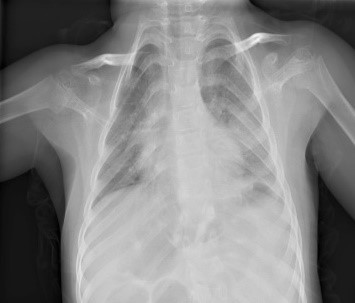

Загальна рентгенографія

Педіатрія